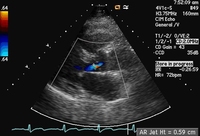

Parasternal long-axis view demonstrating aortic regurgitation jet width and height

From the collections of Dr Sanjeev Wasson and Dr Nishant Kalra; used with permission